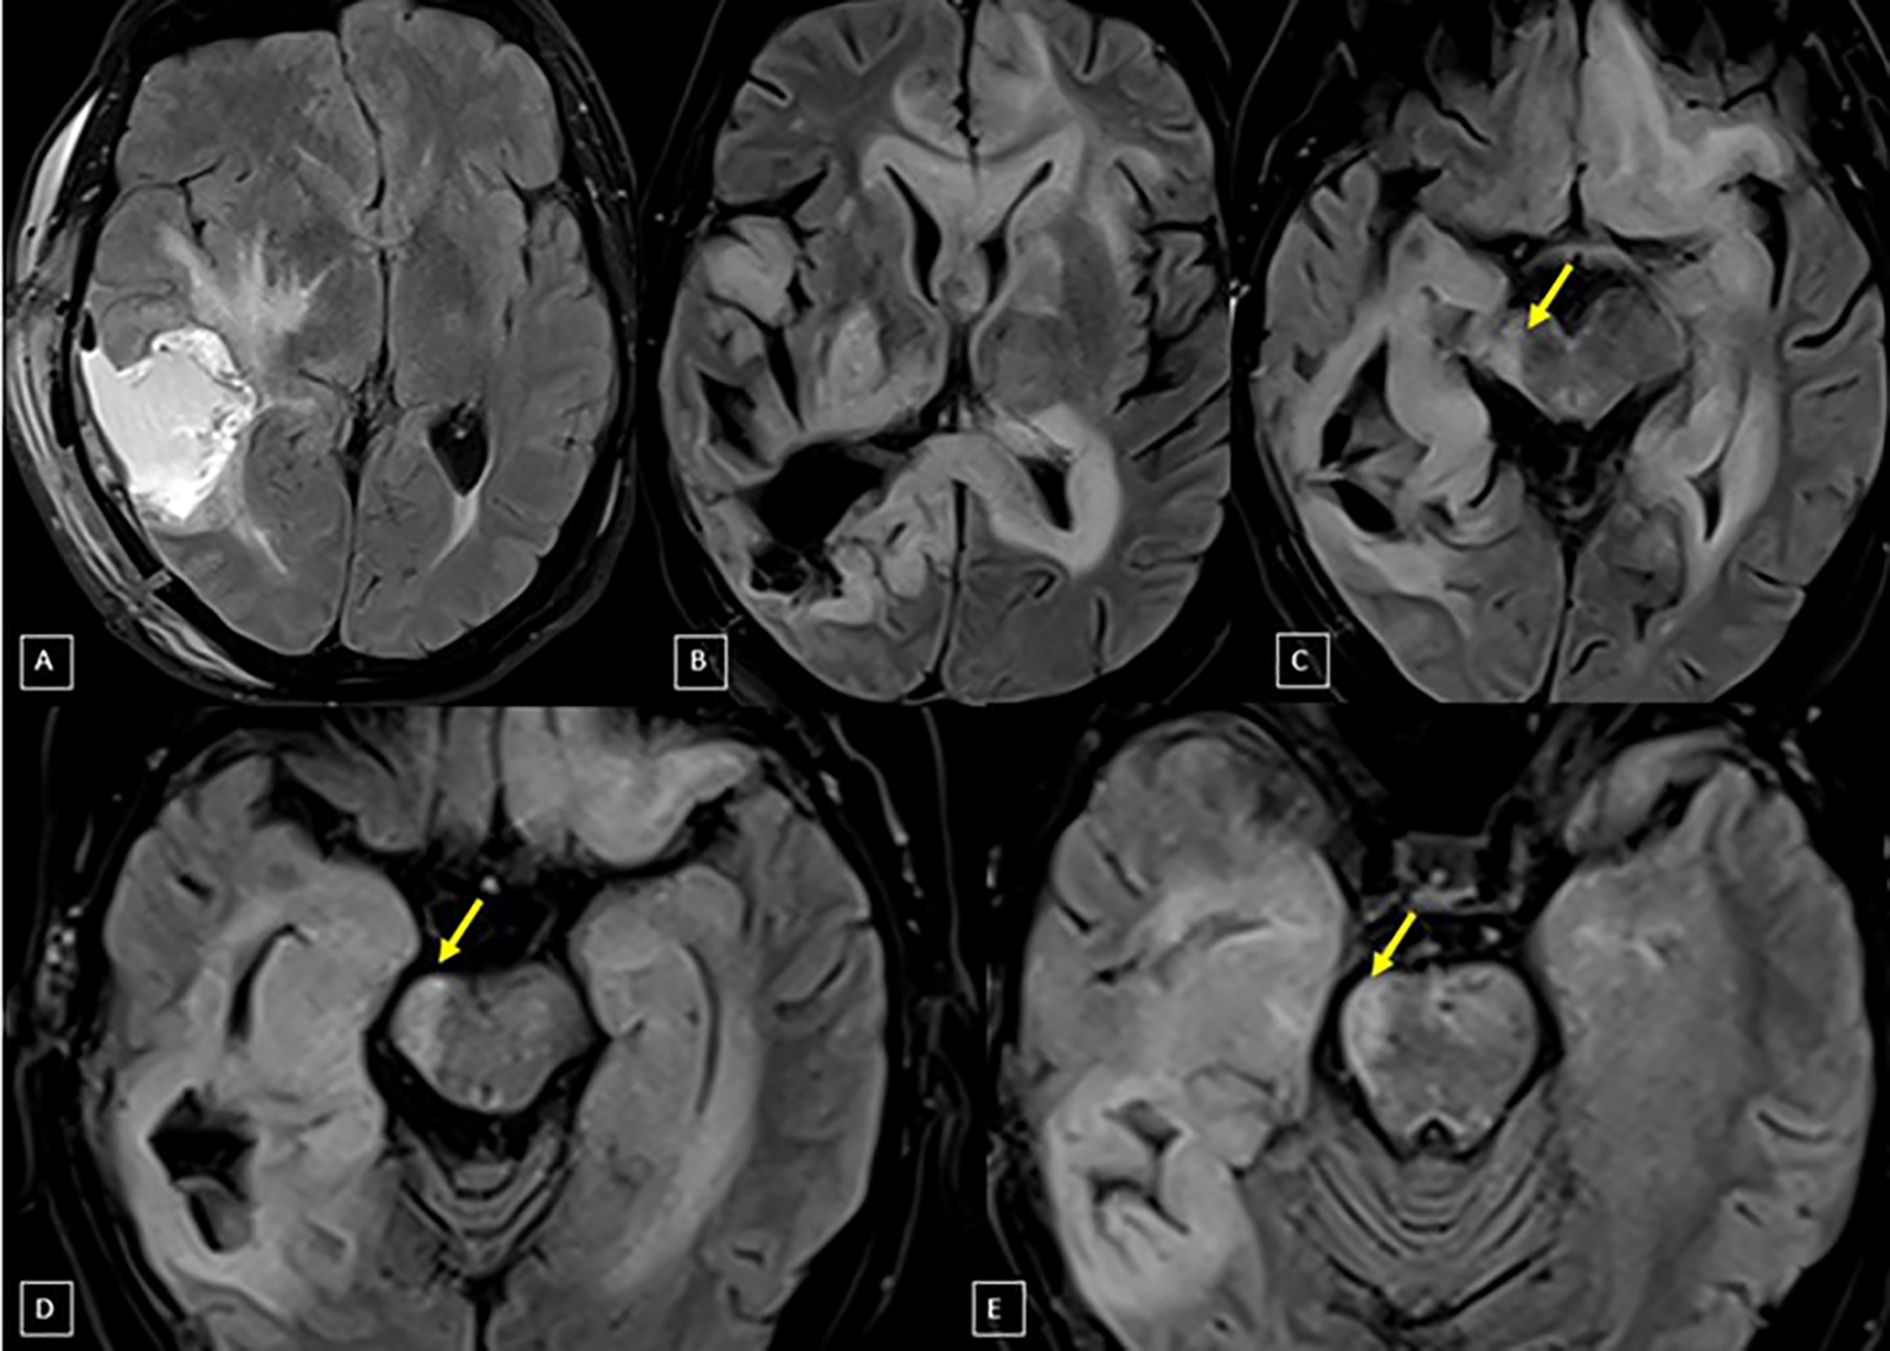

Introduction Wallerian Degeneration of the Corticospinal Tract (WDCT) is a scarcely reported complication of multimodal treatment for high-grade gliomas, which, despite its potential clinical impact, may lead to severe motor dysfunction and impair quality of life. Methodology This retrospective case series describes 13 adult patients with high-grade gliomas treated between 2018 and 2023 who developed imaging findings consistent with WDCT after receiving multimodal treatment. Clinical and radiological data were collected from medical records; a standardized imaging follow-up or functional scoring system was not applied. Tractography was retrospectively available for two cases, enabling its incorporation into radiotherapy planning system for CST precise delineation and corresponding dose estimation. Results WDCT was identified in 13 out of 192 high-grade glioma patients (6.8%). Diagnosis was based on T2/FLAIR hyperintensity along the ipsilateral CST with compatible clinical symptoms. Three cases developed WDCT after reirradiation, and seven (53.8%) had received bevacizumab prior to diagnosis: two during disease progression, two for the treatment of radionecrosis, and three as prophylaxis. Clinical symptomatology was detailed to 11 patients, 72.7% presented with hemiparesis, and 36.4% had seizures. In two cases, retrospective dose-volume analysis revealed CST mean doses ranging from 25.81 Gy to 42.83 Gy. Conclusions This retrospective series highlights WDCT as a potentially underrecognized complication in glioma patients undergoing multimodal treatment. While etiology is likely multifactorial, radiotherapy may play a contributing role. CST delineation, when tractography is available, may support individualized treatment planning, enable better assessment of dose exposure, and help identify patients at higher risk of motor decline. Further prospective studies are warranted to define dose thresholds and assess functional outcomes.